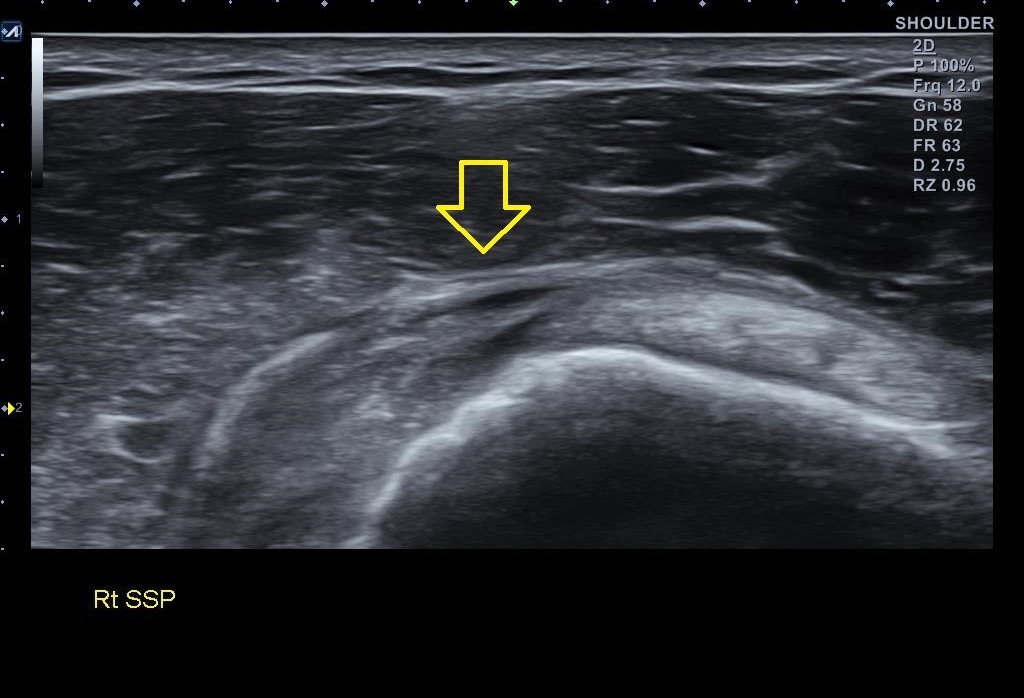

골극이 보이는 상완골 대결절 부위는 극상근 힘줄의 부착부위입니다. x-ray상에 이상 소견이 보인다는건 극상근 힘줄에도 문제가 있을 가능성이 높다는 이야기죠. 힘줄 상태를 확인하기 위해 초음파 검사를 진행했습니다. 결과는...

나 : 초음파 검사 결과를 보니까.... 회전근개 중 극상근이라는 힘줄 파열이네요.

나 : 초음파 검사상 파열 범위와 길이가 아주 심하진 않아서 우선 보존적 치료를 좀 해보고 4주 간격으로 초음파 검사를 몇번 해보면서 지켜봐야 할거 같네요. 지금보다 심해지면 MRI 촬영이 필요할 수 있습니다.

이분의 경우 잔잔한 통증은 오래 되었을 겁니다. 아마 그동안 염증이 반복되면서 골극이 생기고 힘줄이 약해진 상황에서 크로스핏처럼 한번에 힘을 쓰면서 팔을 높게 들어올리는 동작을 하면서 견봉하 공간에서 극상근에 커다란 마찰력이 가해지면서 힘줄이 파열되었을 가능성이 높은 경우입니다.